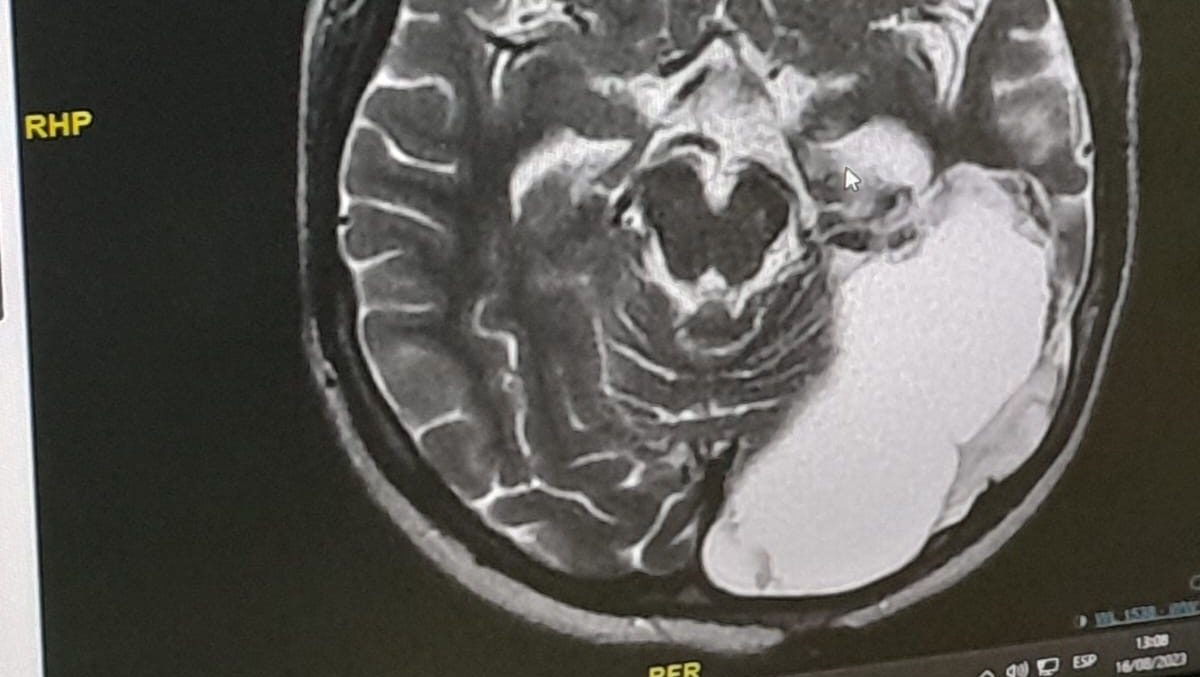

Adriano was detected with a brain tumor on the left occipital side when he was barely 3 years old, today he is 11 years old and we continue in this hard battle.

In all this time they have already performed 4 cranioctomies (brain operations) to be able to remove the tumor but it grows again behaves aggressively, expands and became recurrent, this time it was not only on the left occipital side, also in the hypothalamus and in the ventricles of the brain, this has been accompanied by daily repetitive convulsions, delay of psychomotor development, among other sequelae caused by the tumor and the operations already performed.

On February 17 we were able to admit him to a hospital and they sent us an MRI which with a lot of effort we were able to perform, the neurosurgeon was able to read the images and has asked us again for another MRI to see the growth of the tumor and has referred him to the oncologist so that he can give the appropriate treatment since he is only in charge of the surgical part and the oncologist of the chemotherapy and radiotherapy treatment, and he determines how many sessions he needs, but this is very expensive and that is why I come with all my heart to ask for your support.